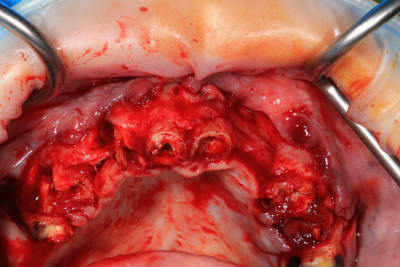

Guide métal avec support clavette, os assez fin : il est prévu un sticky bone complet : donc : lambeau avant extraction, positionnement du guide base et forage des clavettes, positionnement du guide implant, pose des piliers MU, controle des axes prothétique avec le guide pilier, collage des piliers prov sur le bridge a armature métal, occlusion nickel, sticky bone et PRF, sutures suspendues.

Voilà les photos du cas , avec un peu de retard.

Enfin, le cas de la semaine précedente. Guide osseux maison, bridge imprimé. On conserve 26 27. Mais les sinus sont assez antérieurs : on sort au niveau des 4 avec les implants angulés. Malgré le fait de faire un mini comblement sinus droit : l'implant passe la crete, rentre dans le sinus, et retrouve l'os en direction nasal, mais on sort quand meme en 14.

Alors pose d'un implant dans l'alvéole de la 15, aucune stabilité, comblement. A utiliser pour le bridge définitf.